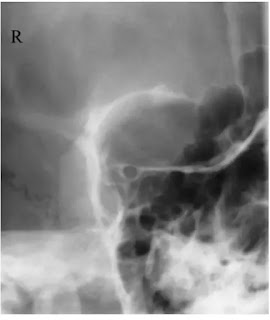

बोनी ऑर्बिट के पीछे optic foramen में optic canal खुलती है। यह canal median sagittal plane से 35° लेटरल तथा OM line से 35° नीचे open होती हैं। इसलिए इसकी pathology के लिए x-ray beam को इसके बीच से गुजारते है। इसमे comparison के लिए दोनों orbit canal का लिया जाता है।

Patient को x-ray table की तरफ मुँह करके खड़ा किया जाता हैं। अब जिस साइड का examination करना है उस साइड check , chin तथा nose को cassette के contact में रखते हैं। orbit के सेंटर ( जिस साइड की orbit का examination किया जाना है ) को cassette या bucky के सेन्टर पर रखते हैं । यह पोजीशन इस प्रकार होनी चाहिए जिससे कि msp टेबल से 35° angle तथा orbito-meatal baseline horizontal से 35° का एंगल बनाये अर्थात।

Direction and centring of the x-ray beam

Collimated horizontal x-ray beam का सेंटर bucky के बीच होना चाहिए। यह बिंदु external auditory meatus से 7.5cm ऊपर तथा 7.5cm पीछे होता है। एक छोटे lead के side marker को orbital margin के ऊपर place कर सकते हैं।